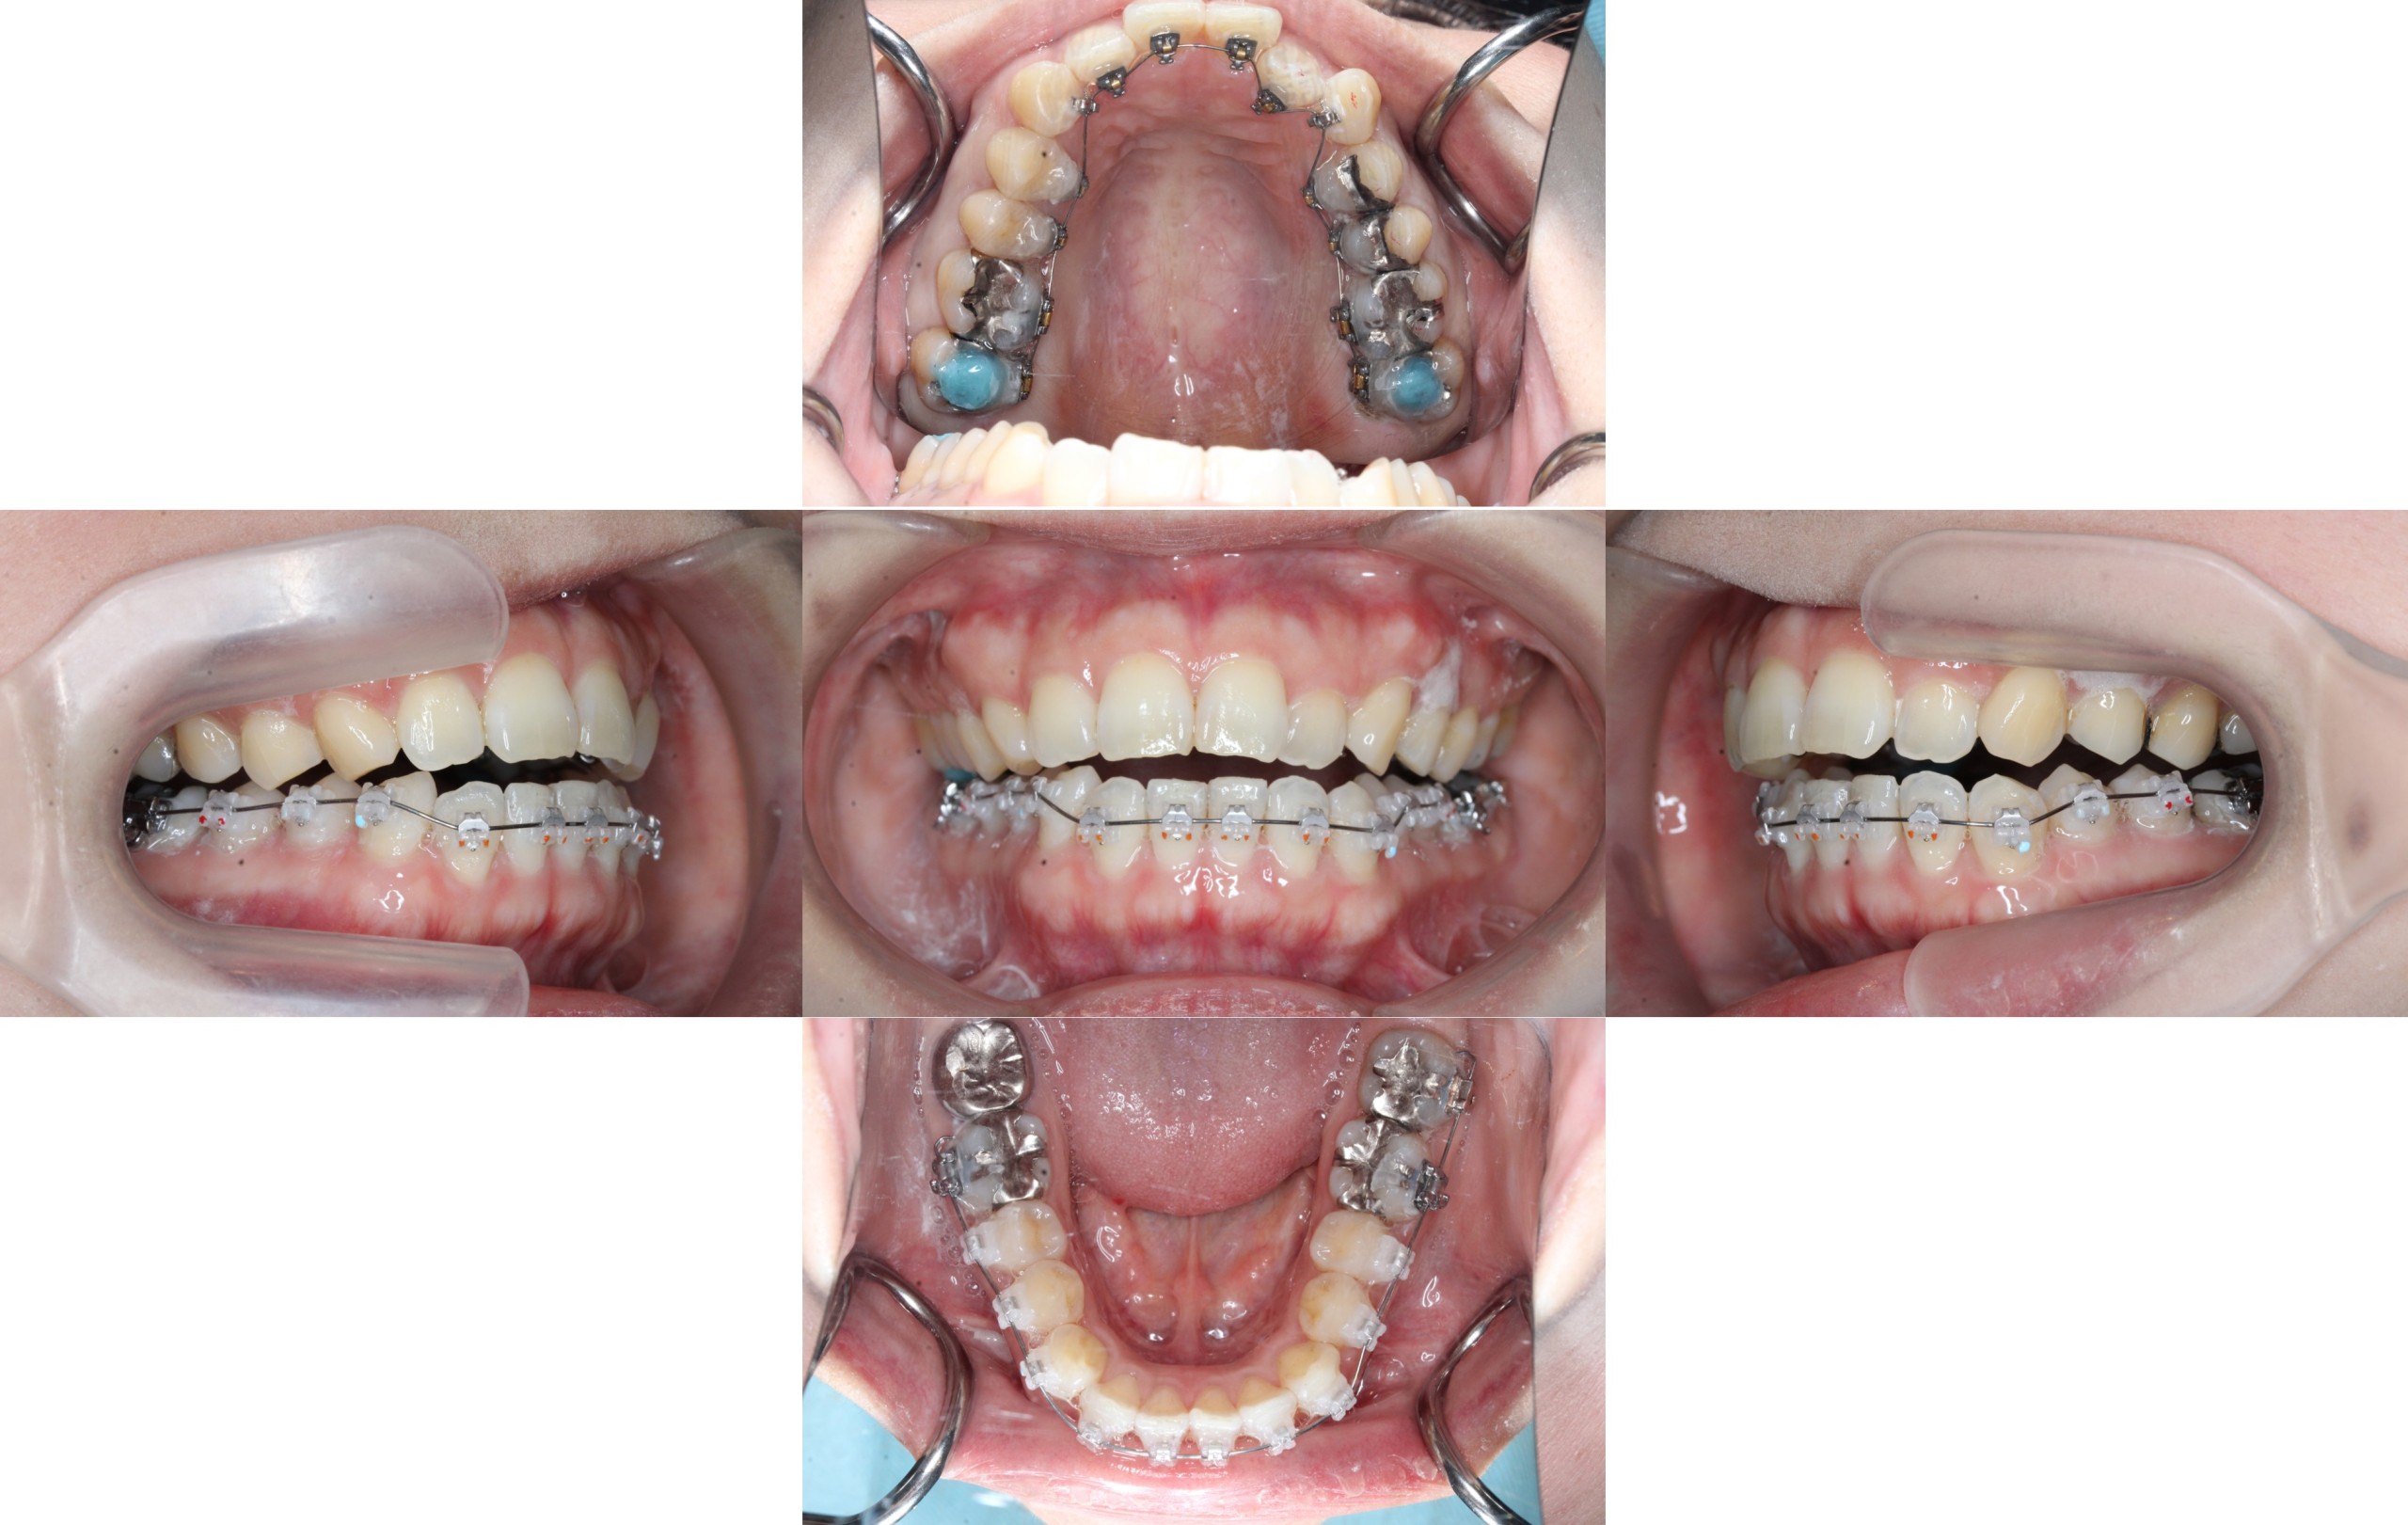

約半年経過